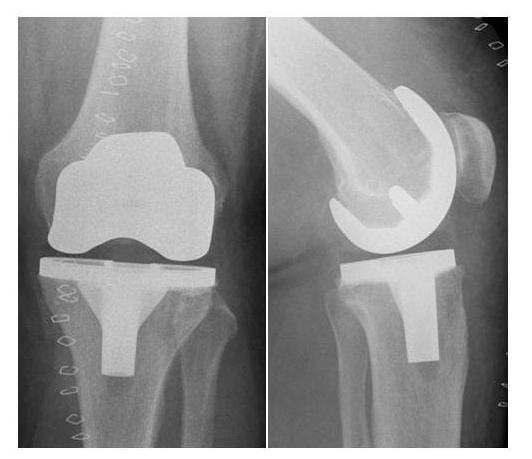

Röntgenbild Prothesenplanung Knie

Die Prothesenimplantation wird anhand eines digitalen Röntgenbildes geplant (links), das Röntgenbild rechts zeigt die zugehörige Implantatlage eines bikondylären Oberflächenersatzes nach der Operation. (Bilder: Orthopädie)